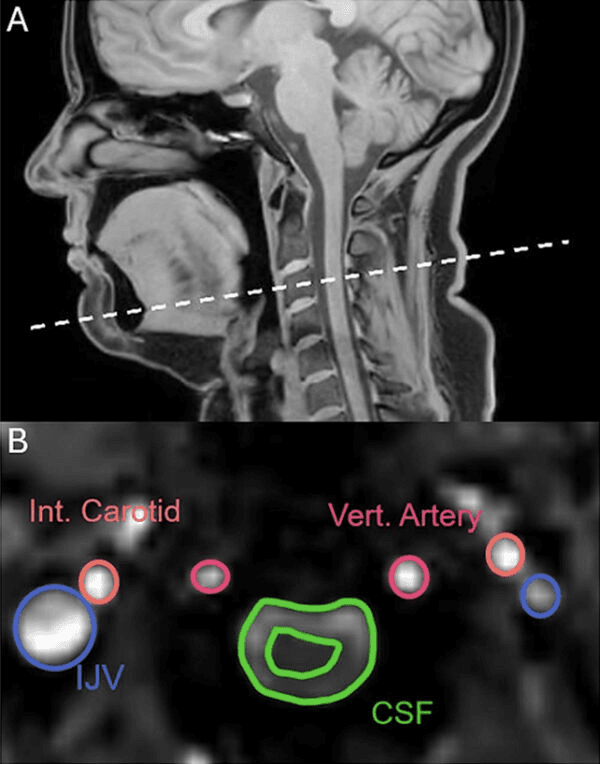

El equipo de investigación utilizó resonancia magnética para escanear las cabezas y los cuellos de 22 participantes sanos mientras se les decía que bostezaran, respiraran profundamente, reprimieran los bostezos y respiraran normalmente. Dado que el bostezo y la respiración profunda comparten mecanismos similares, los investigadores esperaban que se vieran similares en las imágenes. Sorprendentemente, las imágenes revelaron una diferencia clave: a diferencia de las respiraciones profundas, los bostezos expulsan el líquido cefalorraquídeo (LCR) del cerebro.

“El bostezo provocaba un movimiento del LCR en la dirección opuesta al que se produce durante una respiración profunda”, explicó el neurocientífico Adam Martinac a James Woodford en New Scientist.

Esto no se observó en todos los casos y ocurrió con menor frecuencia en los hombres, aunque los investigadores advierten que esto puede deberse a la interferencia del propio escáner. El análisis también reveló que tanto las respiraciones profundas como los bostezos aumentaron el flujo de sangre que sale del cerebro, creando más espacio para que se bombee sangre fresca.

El flujo sanguíneo no cambió de dirección con los bostezos. Sin embargo, durante sus etapas iniciales, el flujo sanguíneo de la arteria carótida hacia el cerebro aumenta aproximadamente un tercio, lo que podría indicar múltiples razones para este comportamiento.